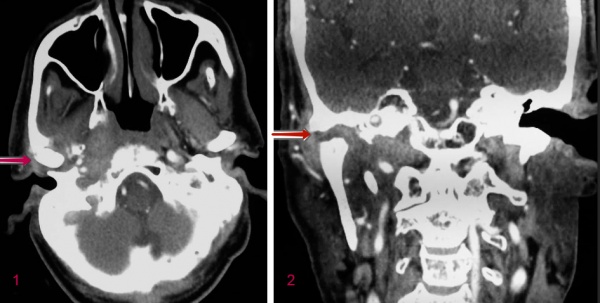

![КТ больного со злокачественным наружным отитом. Эрозия височно-нижнечелюстного сустава и непрозрачность мягких тканей барабанной полости. 1 - аксиальная, 2 – корональная]()

КТ больного со злокачественным наружным отитом. Эрозия височно-нижнечелюстного сустава и непрозрачность мягких тканей барабанной полости. 1 - аксиальная, 2 – корональная